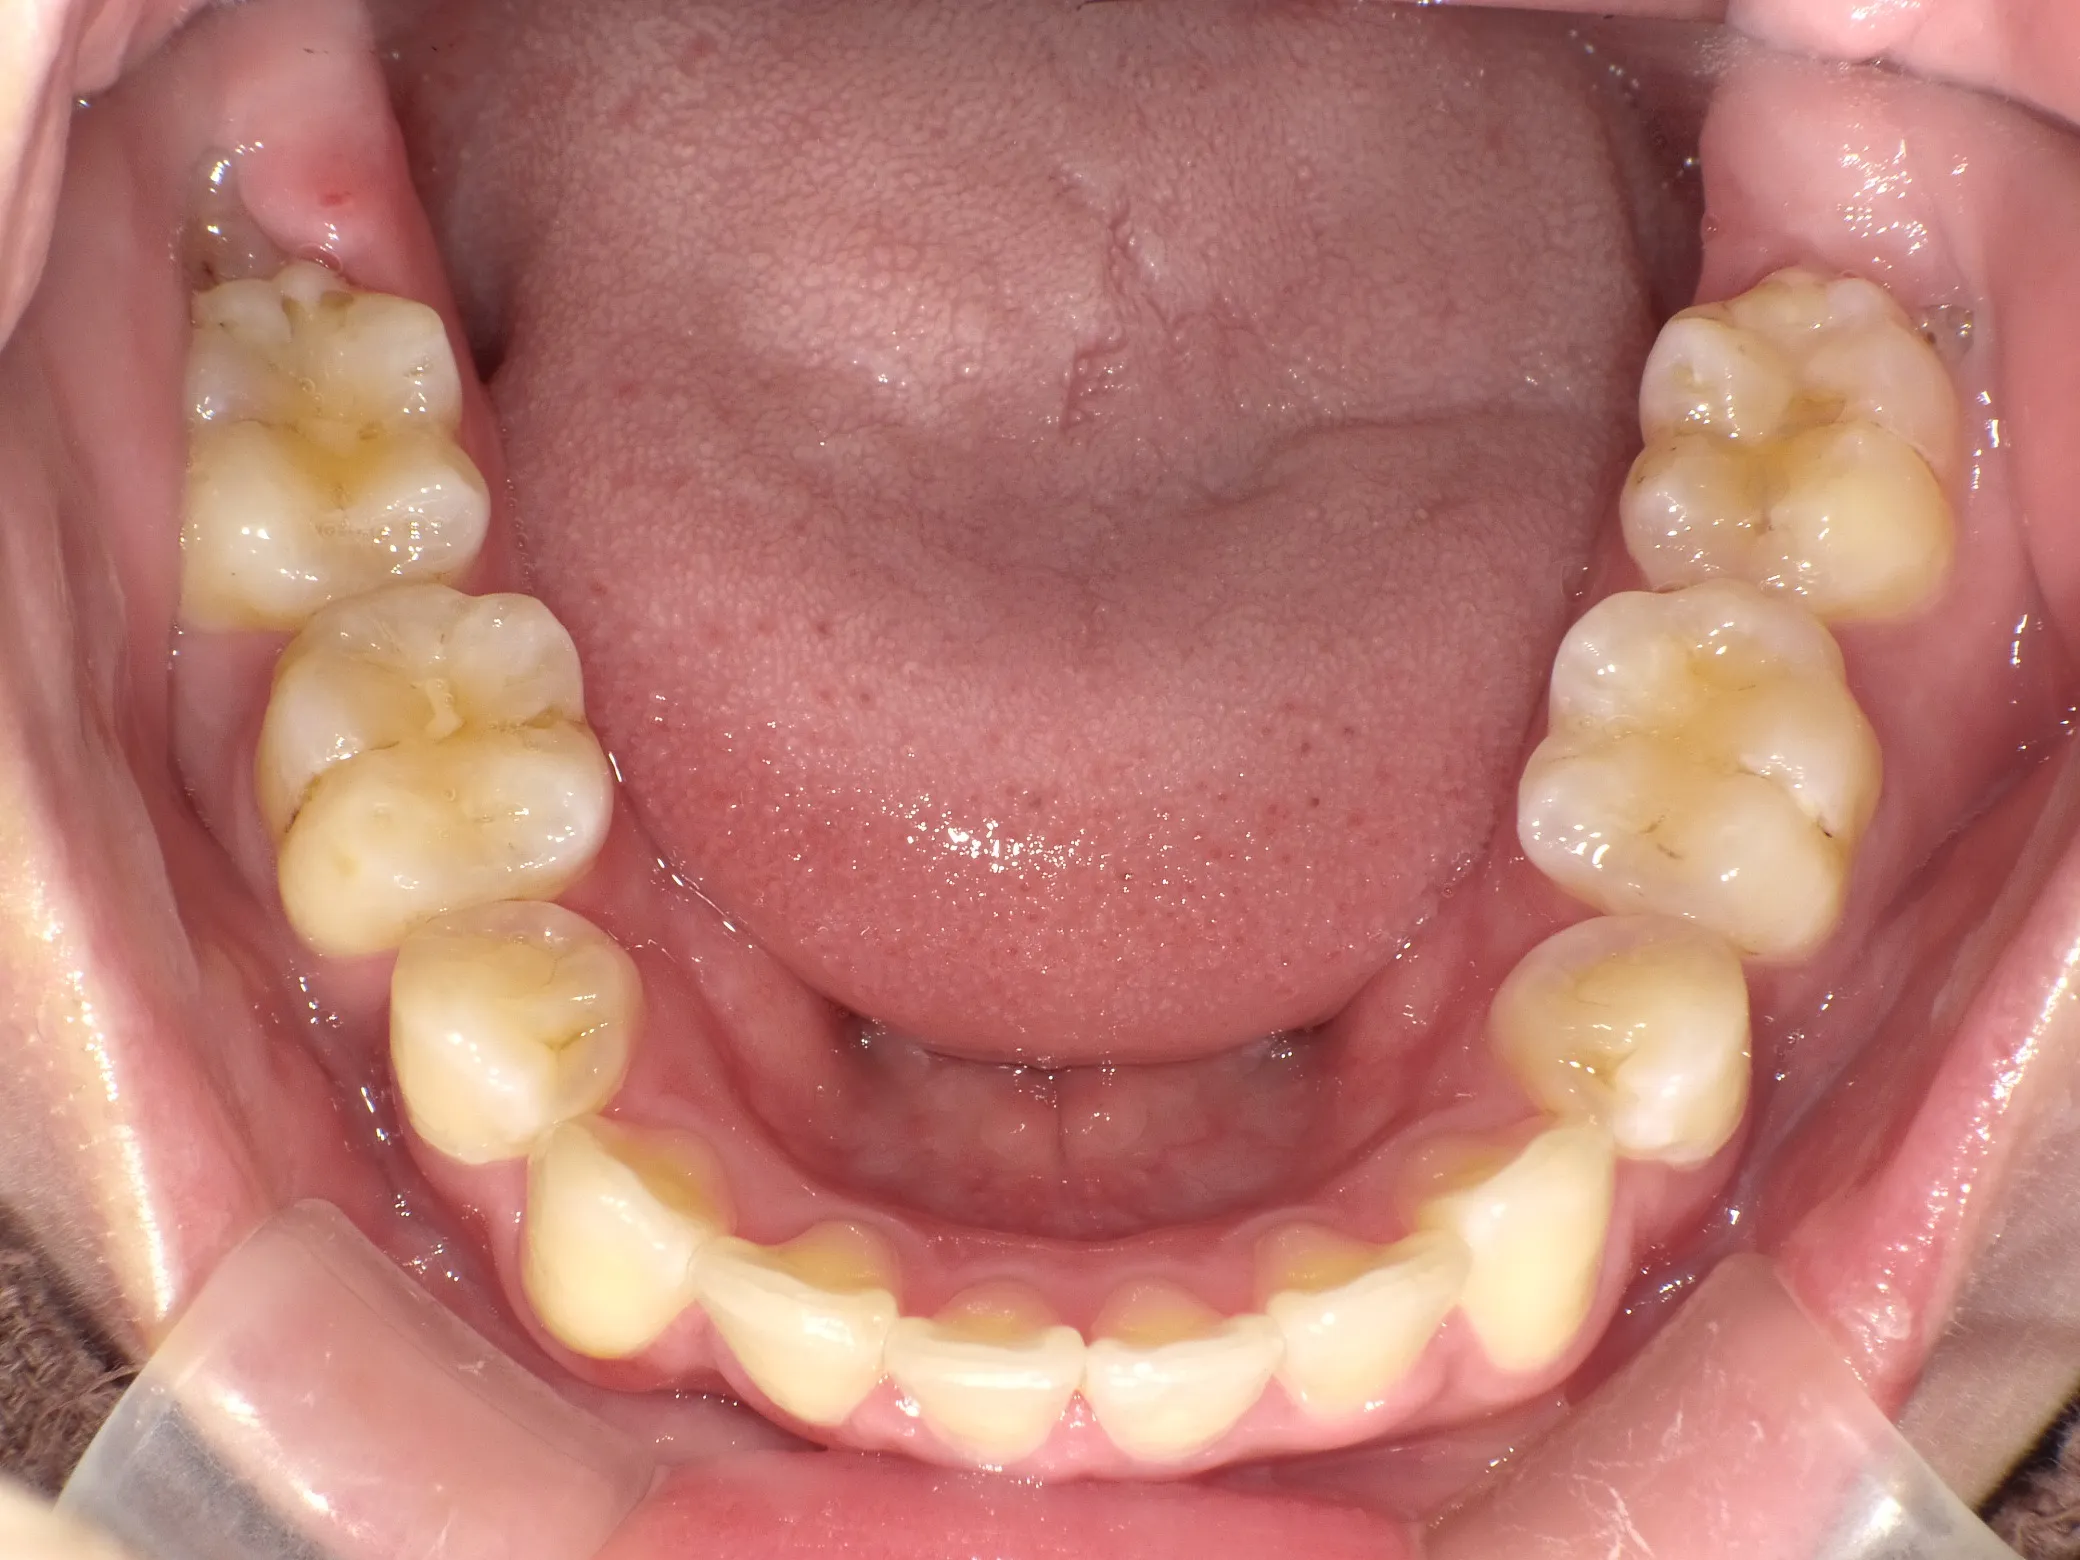

症例③

症例3_治療前 症例3_治療後

治療方法 マウスピース矯正

治療期間 1年8ヶ月

治療総額 850,000円

特記事項 抜歯なし

リスク・副作用 治療の初期段階では痛みや不快感が生じやすくなりますが、1週間前後で慣れます